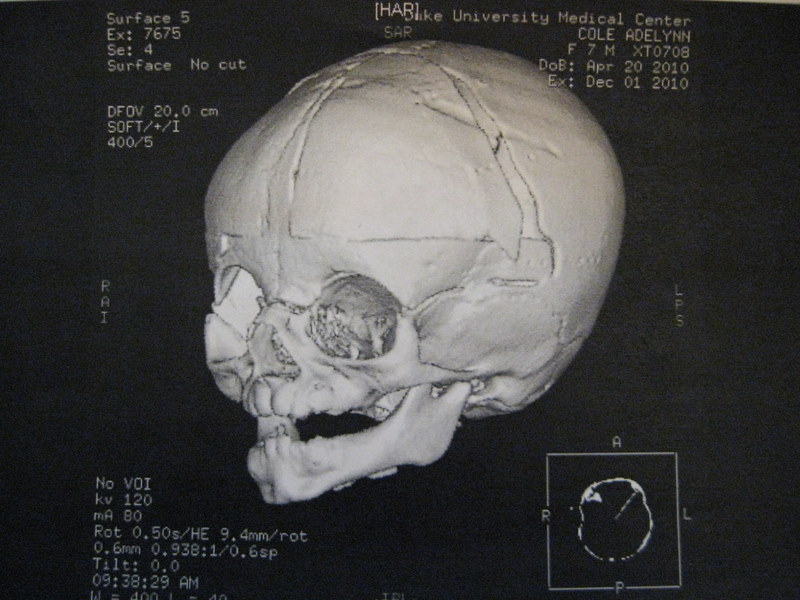

Addy's head continues to look better all the time. The issue now is her eyes. Addy had an ophthalmologist follow-up last week, and it is looking now like eye muscle surgery is pretty much inevitable. This is what the doctor had said last time, but based on the subsequent opinion of her plastic surgeon (and his experience with cranio patients), and based on my own optimistic hopes, I thought we might be able to avoid surgery in the end. Unfortunately, the eye doctor found that her eyes are actually a little worse than last time, and after she spent a little more time explaining things to me, I think I understand why she is pretty convinced it is necessary.

Basically, my assumption has been that Addy more or less has a "lazy eye" that can be corrected with patching and sometimes other therapy. In actuality, the bone around Addy's eyes is shaped such that the muscles are pulling her eyes in unusual directions. This can be corrected by tightening or loosening the muscles to adjust the alignment of the eye.

Another thing I've noticed for a long time is that Addy often tilts her head when she is looking at things. I had thought this was a result of her head being misshapen and bigger (and heavier) on one side than the other. The doctor explained that this is actually also related to her eyes. (I had heard this can happen, but couldn't figure out why.) The doctor explained that there are three sets of muscles on the eye -- some that move them up and down, some side to side, and then another set that (I believe) affects the way the eye moves around in a circle. With Addy's type of cranio, it is common for these last muscles to be pulled in abnormal directions. So she believes Addy's right eye is actually twisted such that she need to tilt her head in order for things to appear level.

This explanation alone made a big difference in my understanding. It also explained to me why it seems that Addy's eyes often seem to be focused in the same direction, but when she looks up, they are always pointed outward from one another, and when she looks way down, they can make her look cross-eyed. If one of Addy's eyes is somewhat twisted in its socket, this makes a lot more sense.

The other problem is Addy's left eye, which tends to be pointed outward from the direction of the right eye. (You can see an example of this in the top picture above.) This is what I had thought was the main problem, that might be correctable with patching. Apparently the doctor thinks that the muscles of her eye are actually pulling it outward as well, and will have to be adjusted in order to align it. (Or perhaps the actual socket is misaligned because of the unusual shape of her head? I'm not sure.) This one still doesn't completely make sense to me, since Addy often does have her eyes pointed in the same direction (i.e., her left eye is not always pointed out). The doctor's explanation was that the eyes tend to point inward when you are looking at something close, but when Addy focuses on objects far away, her eyes point outward. I haven't noticed if this is always true, but it seems probable. If it is true, Addy will have to have surgery on the muscles of both eyes.